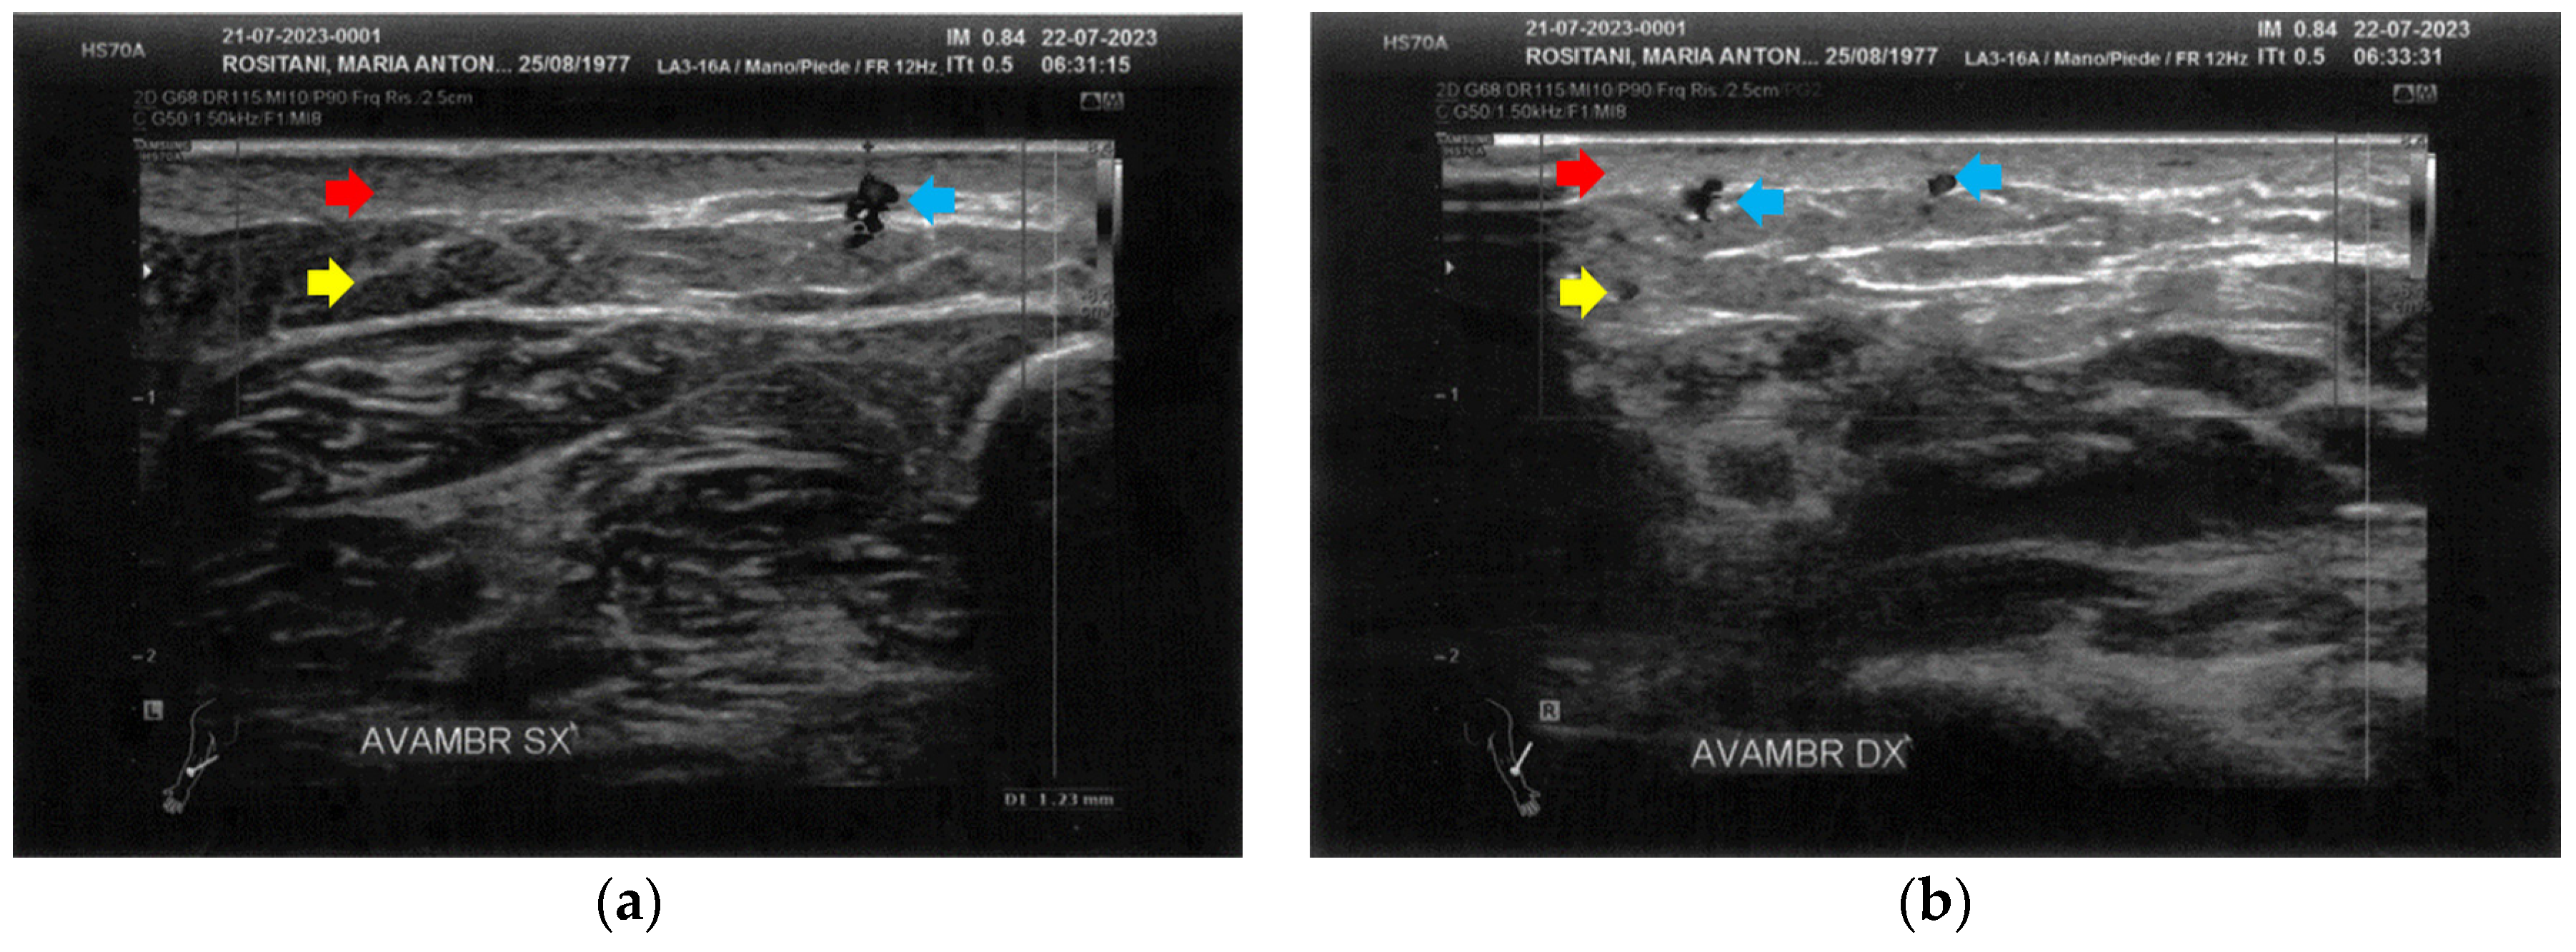

3.1. Basal Imaging Evaluations

3.2. Imaging Evaluations After the Treatment